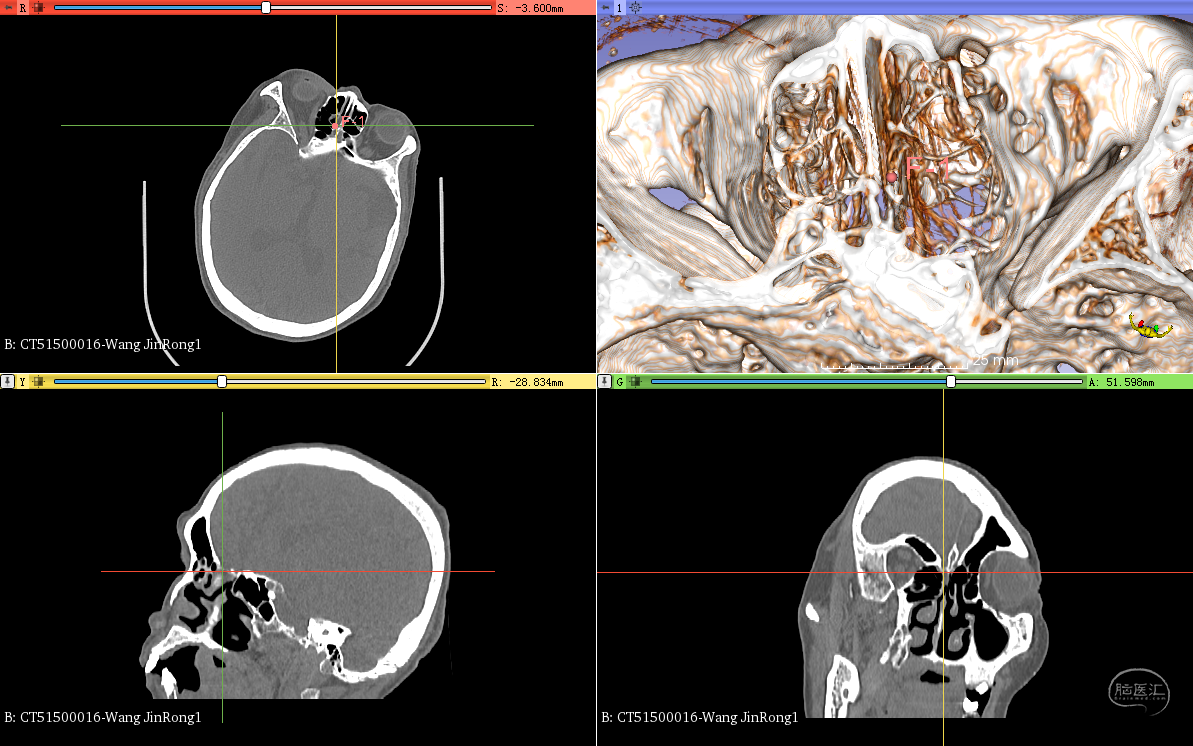

进一步三维CT阅片与重建,导航般了解患者病变位置,患者瘘口位于筛前动脉水平——筛板,嗅凹。

动态观察瘘口位置,制定详细的手术计划。